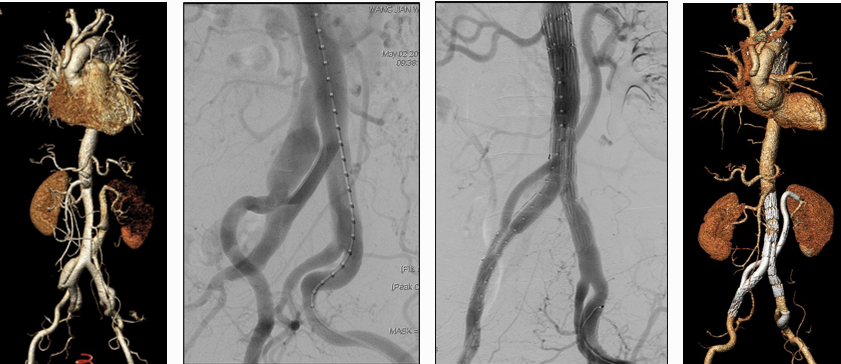

★ WeFlow-EndoSeal™假腔栓塞系统(N=11)

持续假腔血流被认为是TEVAR/EVAR术后动脉瘤样退变的原因。EndoSeal™系统是中国人民解放军总医院第一医学中心血管外科郭伟教授团队自主研发的,一种用于假腔栓塞的设备,能有效阻断假腔回流,促进主动脉重塑。

临床试验早期结果:

纳入11例患者,7例完成术后30天内CTA随访

术后30天假腔100%部分血栓化,真腔直径扩大(12.09→14.53mm),假腔最大直径稳定

1例严重不良事件(术后113天内漏栓塞)